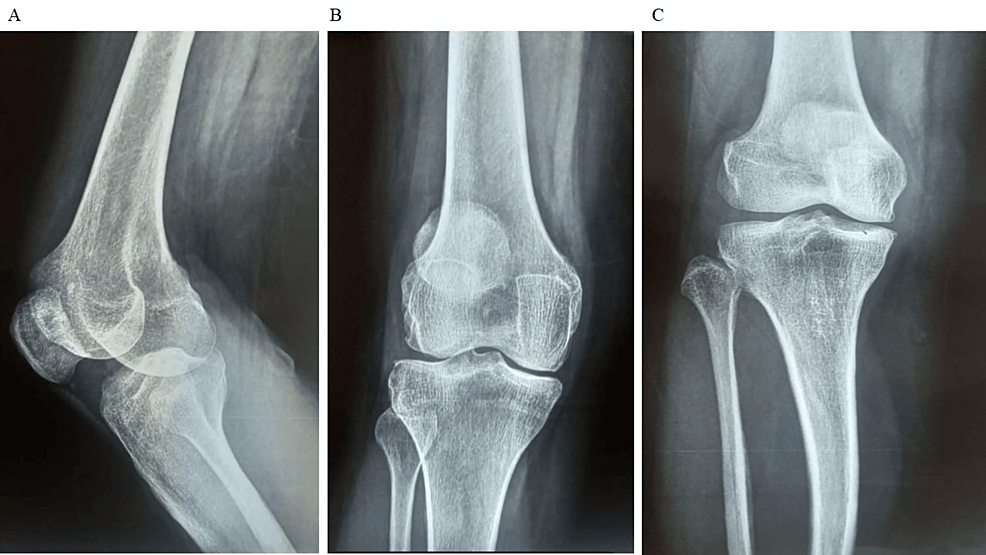

平均WOMAC評(píng)分從基線時(shí)的56.8±11.5下降到六個(gè)月時(shí)的41.2±10.6。此外,還監(jiān)測了不良事件的發(fā)生情況,報(bào)告了七起不良事件,占參與者的28.0%。這些發(fā)現(xiàn)強(qiáng)調(diào)了該治療在六個(gè)月內(nèi)減輕疼痛和改善功能結(jié)果方面的有效性。下圖2顯示了開始干細(xì)胞治療后骨骼的側(cè)視圖和前后視圖。?

圖2:顯示了開始干細(xì)胞治療后骨骼的側(cè)視圖和前后視圖

圖2:A:干細(xì)胞治療后(側(cè)視圖),B:干細(xì)胞治療后前后位 (AP) 視圖,C:干細(xì)胞治療后前后位 (AP) 視圖。